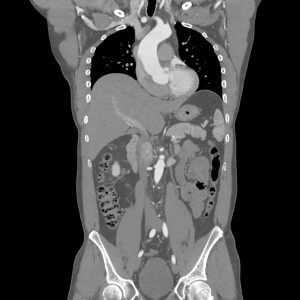

Суть обследования состоит в том, что рентгеновские лучи, пронизывая тело человека, позволяют получить послойное изображение тканей органа с шагом от 0,5 до 10 миллиметров. Выведенная на монитор томографа информация даёт возможность отобразить объёмную картинку конкретного органа.

КТ органов брюшной полости даёт изображение каждого органа в разрезе, при этом картинка не накладывается одна на другую. Компьютерная томограмма показывает наличие заболеваний желудочно-кишечного тракта и забрюшинного пространства, таких как: раковые опухоли, камни, инородные тела, травмы, кистозные образования.

КТ без контраста даёт возможность оценить состояние брюшной полости и каждого органа по отдельности, проверить наличие аномалий развития, а также идентифицировать наличие камней в почках, жёлчном пузыре, жёлчных путях и мочеточнике, увеличение или уменьшение размера органов, изменения в их тканях.

Этот тип исследования помогает установить наличие и количество кальцификатов в артериях или поджелудочной железе, определить аневризму, цирроз, развитие злокачественных опухолей, распространение метастазов.

В случае, если все требования были выполнены, на снимке врач сможет обнаружить место, размеры и количество очагов воспаления, камней, новообразований, тромбоза, и иных нарушений, степень их распространения.

Компьютерная томография органов брюшной полости - прогрессивный метод обследования внутренних органов и забрюшинного пространства, который позволяет получить послойные снимки структур тканей. Он отличается высокой точностью, безболезненностью и информативностью результатов. В результате проведения КТ, можно обнаружить первичные и вторичные объёмные образования, абсцессы, поражения забрюшинных узлов, травмы и аневризмы, распространение метастазов. Ценность полученной информации заключается в том, что с её помощью можно выявить патологии на самых ранних стадиях, разработать стратегию лечения, следить за эффективностью его проведения.